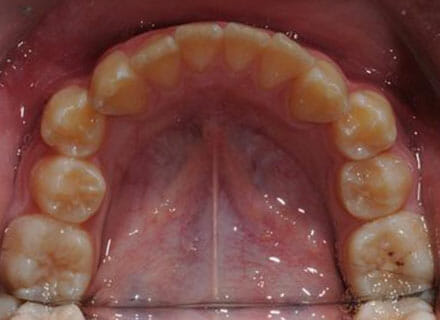

Fixing protruding teeth upper and lower and crowding – no extractions

this patient didn’t like the teeth because they pushed forwards and were sticking out and pushing out her lips. She thought that she looked like she had too many teeth and not enough space. In 12 months we pulled all the teeth back, pulled them together, and lined them all up. No teeth were extracted because we made room by expanding the jaws.